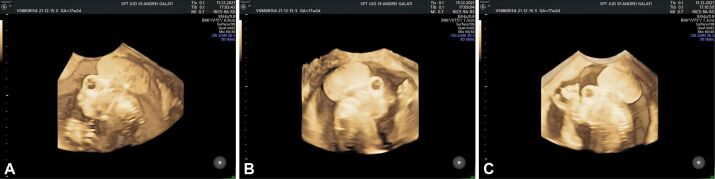

眼轮畸形是一种胎儿畸形,其特征是眼眶和睫状上脊上方的小腿完全或部分缺失。这种畸形的确切机制尚无定论,但发育第四周间质迁移紊乱是最常见的记录。尖头畸形的主要声像图特征是无小腿和大脑背侧隆起(米老鼠头)。由于颅骨的正常骨化过程,只有在妊娠 11 周后才能确诊。早期发现极为重要。预后极差,因此选择终止妊娠是首选的治疗方法。本文将根据一例妊娠晚期诊断病例,讨论我们所了解的胎儿颅骨畸形的病因和超声特征。

Acrania is a fetal malformation characterized by complete or partial absence of the calvaria above the orbits and supraciliary ridge. No exact mechanism is demonstrated for this anomaly but disturbances in mesenchymal migration during the fourth week of development are the most documented. The key sonographic features of acrania are absent calvaria and dorsally bulging brain (Mickey Mouse head). Due to the normal process of ossification of cranial bones, the diagnosis can be established only after 11 weeks of gestation. Early detection is extremely important. The prognosis is extremely poor so elective termination of pregnancy is the treatment of choice. In this paper, we discuss the things we know about pathogeny and ultrasonographic features of fetal cranial malformations based on a case diagnosed late during gestation.